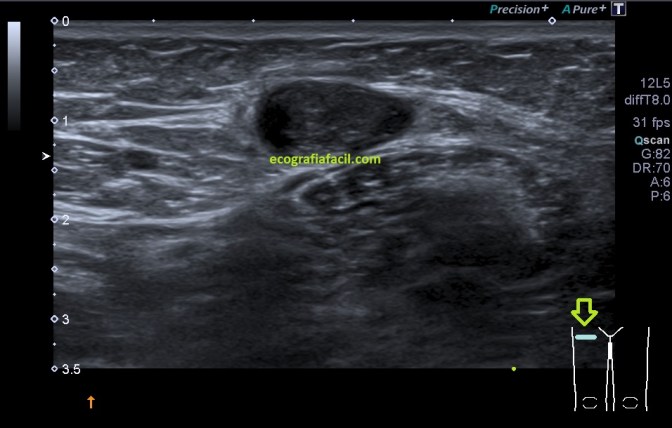

Desde la ingle derecha barrí inferiormente con el transductor, mi sorpresa, a muy pocos centímetros una imagen anecoica redondeada que parecía contener algo, imagen 2, lo primero que pensé fue en una adenopatía, pero al girar la sonda vi que la estructura se alargaba, imagen 1, era tubular en longitudinal y circular en transverso, además pude asegurarme de que en su interior había contenido ecogénico a lo largo de ella. Contenido que no era móvil, es decir, estaba adherido a la capa interna del vaso.

La estructura era ecográficamente hiperecogénica, irregular, ocupaba parte de la luz del vaso, en algún tramo, casi en su totalidad.